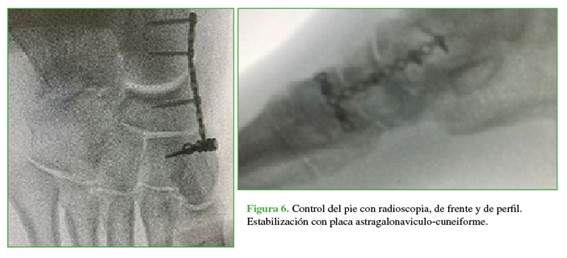

Luego de una semana de seguimiento y tras constatar la correcta evolución de las partes blandas (Figura 4), se procedió a la fijación definitiva. En el quirófano, se ubicó al paciente en decúbito dorsal y se colocó un manguito hemostático en el muslo. Se efectuó inicialmente una incisión dorsomedial centrada a nivel astragalonaviculo-cuneiforme donde se pudo visualizar la luxación incoercible del hueso navicular una vez retirada la clavija de Kirschner (Figura 5). Se decidió la reducción abierta aplicando tracción axial y compresión lateral, con estabilización temporal mediante una clavija de Kirschner para, luego, con una placa bloqueada en T de 2,0 mm (Figura 6), realizar la fijación astragalonaviculo-cuneiforme definitiva. Se continuó con un abordaje dorsolateral a nivel de la articulación calcaneocuboidea donde se visualizó una fractura de tipo hundimiento articular a nivel del calcáneo con subluxación plantar calcaneocuboidea. Se utilizó un impactador óseo para elevar la superficie articular hasta su posición normal, se colocó un injerto esponjoso autólogo de la tuberosidad posterior del calcáneo, se recuperó la congruencia articular y se fijó con una placa calcaneocuboidea en puente bloqueada tipo T de 2,0 mm (Figuras 7 y 8).

En primer lugar, se estabilizó la columna medial, ya que no tenía ninguna fractura y eso permitió recuperar la longitud adecuada una vez reducidas las articulaciones. En segundo lugar, se fijó la columna lateral que sí presentaba fracturas conminutas. Se cerraron las heridas por planos y se inmovilizó con férula suropédica. Se solicitaron radiografías de pie, de frente y de perfil sin carga en el posoperatorio inmediato y, con carga, a los tres, seis y 12 meses de seguimiento (Figura 9).